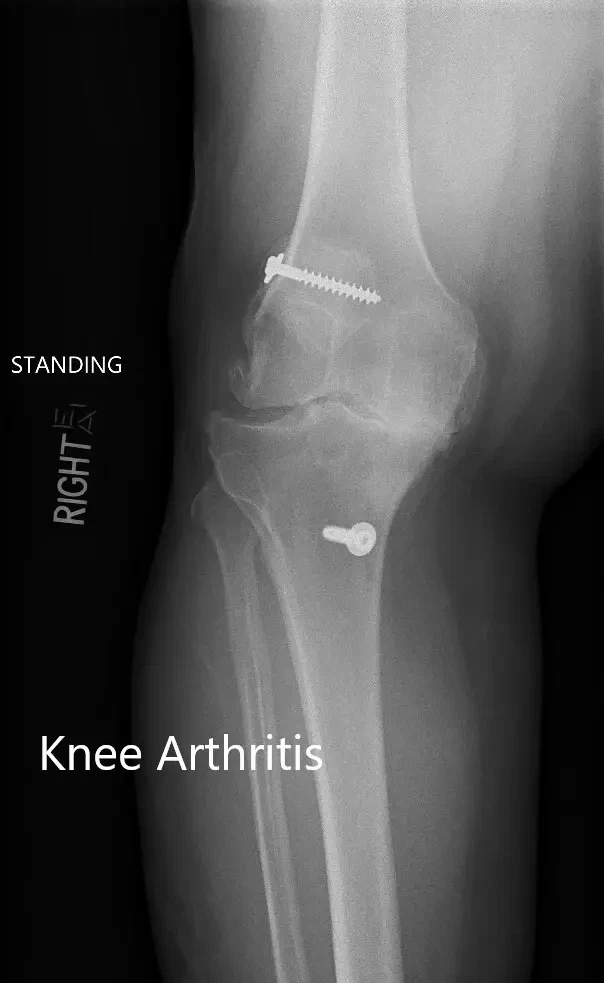

Preoperative X-ray showing the AP and lateral views of the right knee with retained screws consistent with ACL reconstruction.

Preoperative X-ray showing the AP and lateral views of the right knee with retained screws consistent with ACL reconstruction (image 3)